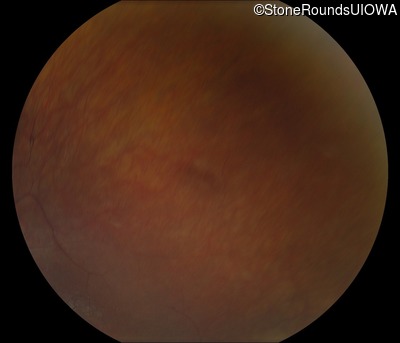

Fundus Photography - Right - 5/180

Exemplar